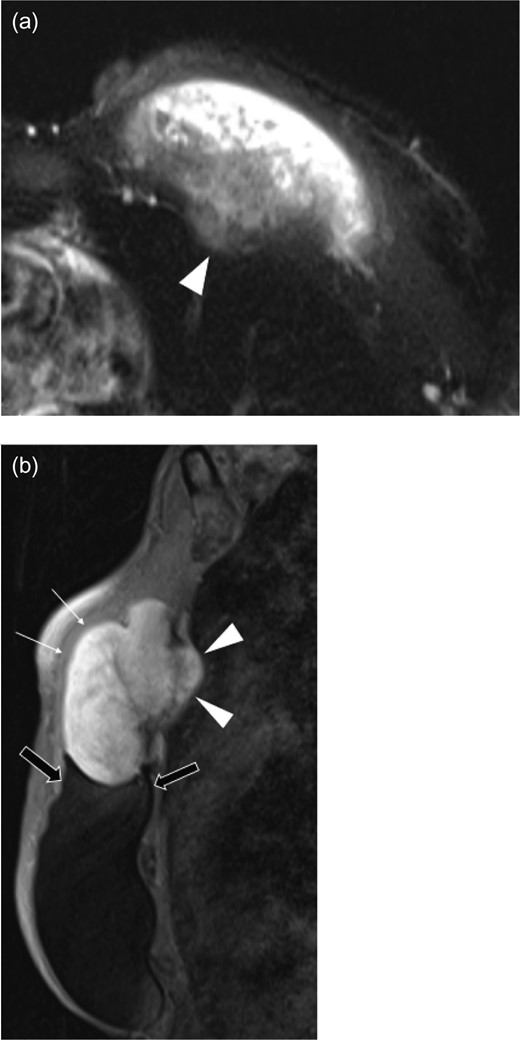

Ultrasound revealed a well-defined, heterogeneously, hypoechoic mass abutting the superior medial portion of the intact implant (Fig. 2). The lateral aspect of the mass demonstrated a characteristic ‘fascial-tail’ sign described by Huang et al. [8] as the linear extension of the tumor along the fascial planes diagnostic of fibromatosis. The mass extended into the intercostal space posteriorly. There was evidence of increased vascularity. The axilla was evaluated and showed no suspicious axillary lymphadenopathy. Magnetic resonance imaging (MRI) without contrast demonstrated an 8.1 × 4.7 × 7.1 cm3 slightly lobulated mass abutting the un-ruptured silicone breast implant (Fig. 3). The mass extended into the anterior intercostal space between the second and third ribs, with no definitive involvement of the ribs. On T1 weighted sequences, the lesion was heterogeneous and had low signal; signal intensity was hyperintense on gradient-echo imaging. The pectoralis muscle was seen extending over the mass but without definitive involvement.

Axial T2 weighted half-fournier acquired single-shot turbo spin echo (HASTE) (a), and sagittal fat suppression (b) images of left breast mass. The pectoralis major muscle (white arrows) overlies the large mass that extends into the intercostal space (arrowheads) between the second and third ribs. The lobulated mass is in direct contact with the breast implant (black arrows).